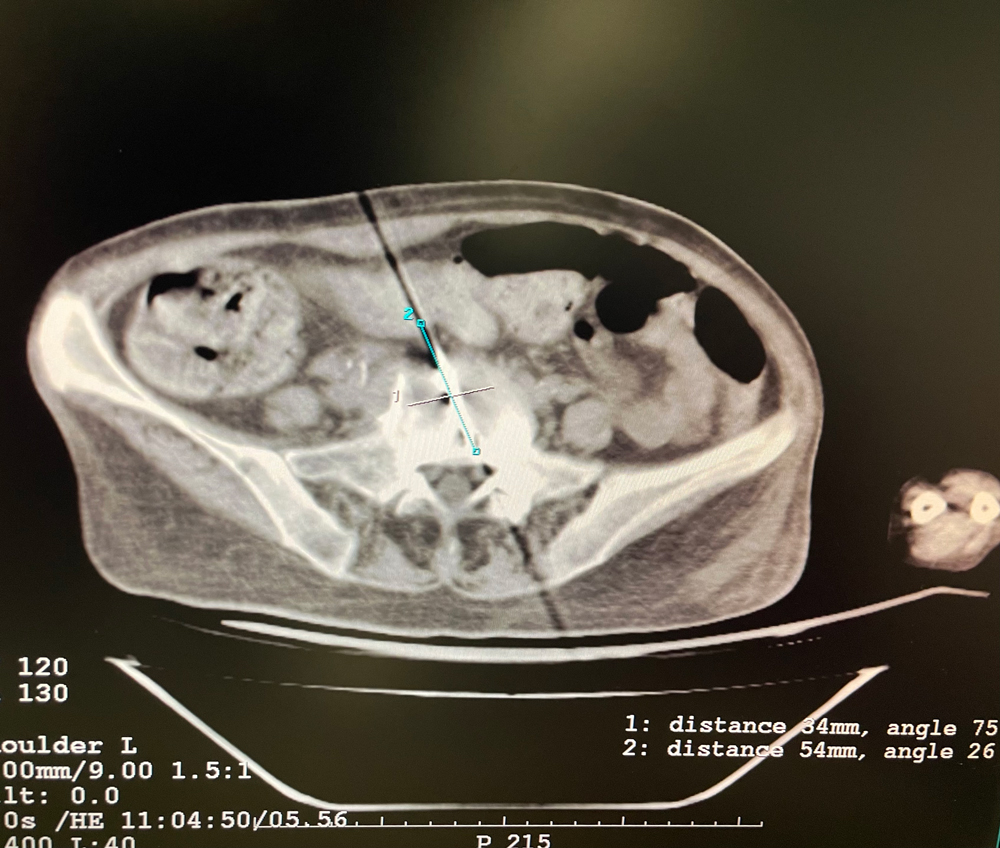

女,56歲,肺轉(zhuǎn)移瘤,骶骨、左側(cè)肋骨各一轉(zhuǎn)移灶,病灶大小均為5cm。骶骨轉(zhuǎn)移灶、肋骨轉(zhuǎn)移灶各進行2個凍融循環(huán)。患者術(shù)后狀況良好。